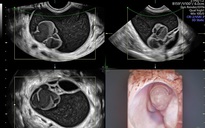

"Vì vậy, khi có biểu hiện đi tiểu nhiều lần kéo dài, đặc biệt kèm theo các dấu hiệu như tiểu buốt, tiểu đêm, tiểu không hết hoặc mệt mỏi, việc thăm khám là cần thiết để xác định nguyên nhân. Các phương tiện chẩn đoán cơ bản như xét nghiệm nước tiểu, đo đường huyết và siêu âm hệ tiết niệu có thể giúp định hướng chẩn đoán và đưa ra hướng điều trị phù hợp" - BS Quyền lưu ý thêm.